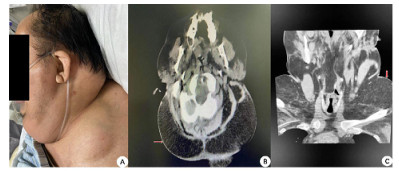

入院查体:患者呈昏迷状,双侧瞳孔等大等圆,直径3 mm,对光反射迟钝,颈部(图 1)和肩部(图 2)分别可见7 cm×4 cm及5 cm×6 cm大小软组织肿胀,质软,腹部及双侧大腿内侧(图 3)可见5 cm×6 cm软组织肿胀,质软,双肺呼吸音粗,双肺可闻及少许湿啰音,心律齐,各瓣膜听诊区未闻及病理性杂音,腹部膨隆,腹部查体不配合。入院后相关检查见表 1,腹部超声提示脂肪肝,心脏超声示左室壁运动弥漫性减低、左室壁肥厚,左室射血分数47%。

| A:患者枕部、肩部、背部脂肪隆起;B:颈部CT平扫(轴位-枕部皮下脂肪影增多);C:颈部CT平扫(冠状位-肩部皮下脂肪影增多) 图 2 患者枕部、肩部及背部病变(红色箭头所示) |

入院后给予呼吸机辅助通气,美罗培南抗感染、维生素B1肌注、营养支持等治疗,患者神志逐渐恢复,可自主睁眼,但不能按指令动作,呼吸机条件逐渐下调,并于2月4日成功脱机拔管。复查相关实验室检查见表 2,行头颅CT示脑室系统扩大,脑沟、脑裂稍宽,脱髓鞘改变;颈部CT示颈部大量脂肪沉积(图 1、图 2);胸部CT示双肺散在斑片影,考虑感染;腹部CT示腹腔及皮下脂肪影增多(图 3)。结合患者既往长期大量饮酒史、查体及影像学表现,考虑诊断:马德龙病、Wernicke脑病。患者不能配合指令动作,未行头颅磁共振检查。